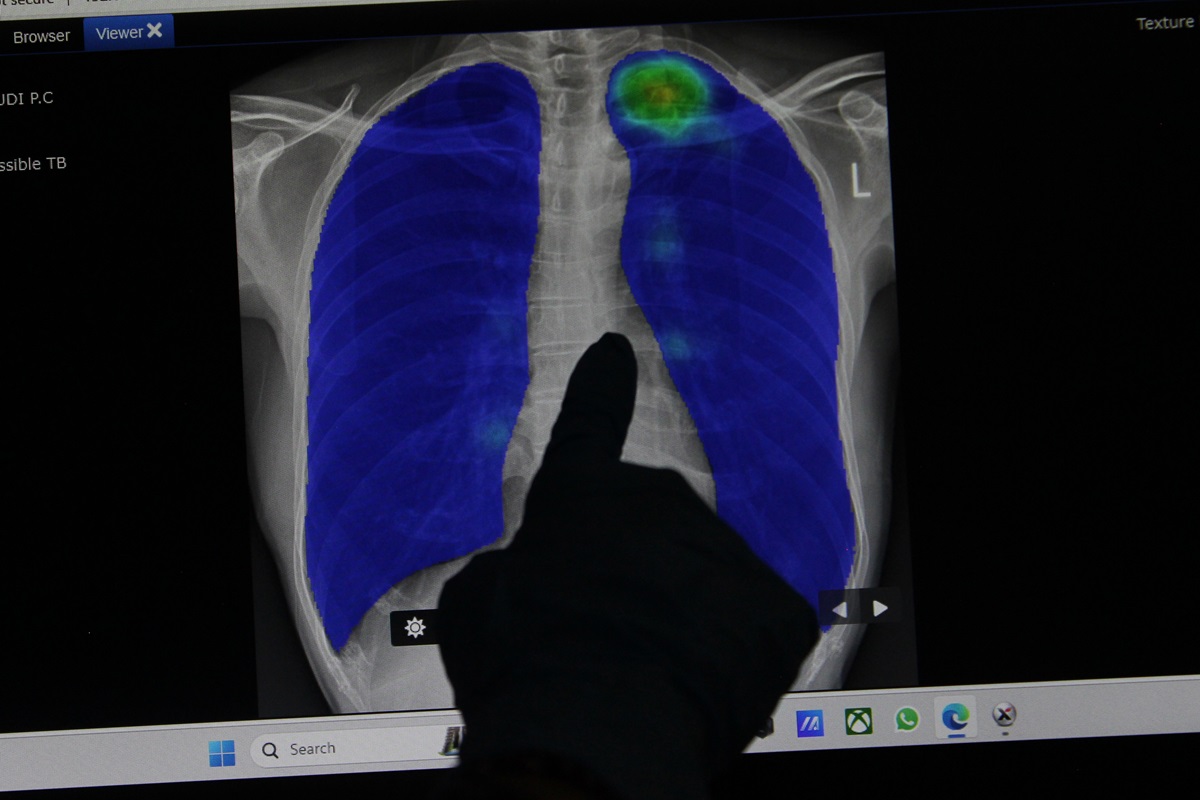

INDONESIA harus belajar dari India terkait tengan penanganan penyakit tuberculosis (TB). Seperti ketahui Indonesia merupakan penyumbang kasus tuberkulosis terbanyak ke dua di dunia. Di peringkat satu ialah India.

Ketua Majelis Kehormatan Perhimpunan Dokter Paru Indonesia (PDPI) Tjandra Yoga Aditama mengungkapkan, pada April 2024 India mengeluarkan India TB Report 2024 yang diedarkan luas ke masyarakat.

"Setidaknya, beberapa hal dalam India TB Report 2024 dapat kita kaji untuk pengendalian tuberkulosis di negara kita," kata Tjandra dalam keterangan resmi, Selasa (28/5).

Menurut dia, salah satu pencapaian amat penting dalam pengendalian TB di India ialah menurunkan angka kematian akibat Tuberkulosis (TB).

Angka kematian TB India turun cukup tajam, dari 28/100.000 penduduk di tahun 2015 menjadi 23/100.000 penduduk di tahun 2022. Data lain juga menunjukkan bahwa kematian akibat TB India turun dari 494.000 di tahun 2021 menjadi 331.000 di tahun 2022.

Keberhasilan kedua program TB India adalah negara itu berhasil mencapai target 2023 mereka yaitu memulai pengobatan pada 95% pasien mereka.

Selain itu, dalam pelaksanaan program TB India, sebagian besar kasus ditangani fasilitas pelayanan kesehatan pemerintah, tetapi peran swasta juga terus meningkat. Ada 33% kasus yang ditangani swasta di tahun 2023, atau sekitar 840 ribu kasus. Angka ini jauh meningkat dari 190.000 kasus yang ditangani swasta di tahun 2015.

"Pemerintah India juga menyampaikan lima faktor risiko yang menjadi tantangan dalam pengendalian TB mereka, yaitu kurang gizi, HIV, Diabetes, alkohol dan kebiasaan merokok," beber dia.

"Akan baik kalau pengalaman dari India juga dipakai sebagai salah satu pertimbangan dan kajian dalam pemerintah mengambil kebijakan TB di negara kita, tentu sepanjang memungkinkan dijadikan benchmark pula," pungkas dia. (Z-3)